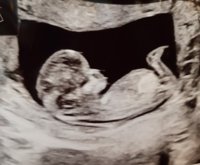

Ekassa ultrassa käyty! Kaikki hyvin pikkukaverilla. Kovasti vilkutteli siellä ja yritti piiloutua niin että oli hieman haastavaa saada mittoja. Niskaturvotusta 0,9 mm. Laskettu aika muuttui päivällä eteenpäin ja on siis 3.3. :happy:

Nt-ultrasta kohti kotia ajellaan :Heartred viikot ja LA pysyi samassa, 4.3 ootellaan saapuvaksi!

Lukemaksi saatiin 0,4 ja kovasti meillä oli vauhdikkaan oloinen vauva tuloillaan :happy:

Nt-ultrassa käyty tänään ja kaikki vaikutti olevan hyvin. Turvotusta oli 1,3 mm joka lienee normaali, riskiluvut saadaan vasta myöhemmin tietoon. Mutta suuri helpotus oli tämä käynti, kauheasti stressasin etukäteen :)